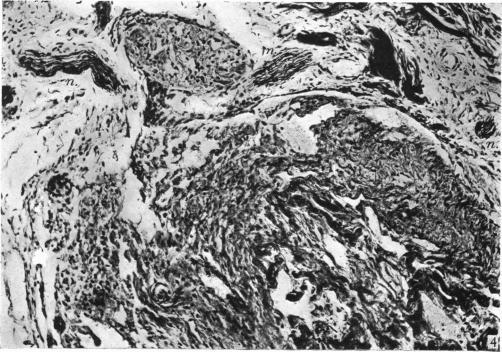

The nervous and vascular relations of the pineal gland.

J Anat. 1940 Jul;74(Pt 4):471-492.3.